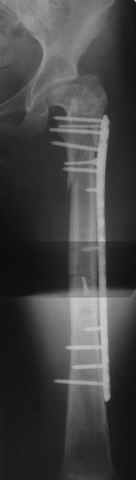

Уважаемые коллеги, приношу извенения за молчание. Готовили материал и боялись писать раньше времени. Все хотели убедиться в том, что после операции все будет спокойно. Спасибо за отклики и советы. К сожалению, гамма-гвоздя, штифтов с возможностью установки более 2-х блокирующих винтов у нас нет. Зато нашли достаточно длинную пластину с угловой стабильностью. После проведения предоперационной подготовки и планирования выполнили остеосинтез. В условиях рентгеноперационной, после репозиции дистрактором из одного разреза 5см в проксимальном отделе подкожно установили пластину. Пришлось выполнить дополнительный разрез до5см в проекции перелома диафиза в средней трети, из которого удалось репонировать перелом и выполнить фиксацию стягивающим винтом. Затем все завершилось наложением пластины с угловой стабильностью. Пластина оказалась достаточно длинной, что позволило перекрыть все переломы с фиксацией каждого отломка минимум 5-ю винтами. Синтез достаточно стабилен. Пациентка активизирована на 3-и сутки(снимки прилагаются). В настоящий момент пациентка выписана на амбулаторное лечение. Еще раз, огромное спасибо всем за помощь в выборе тактики и просто совете. С уважением Украинский Е.

Прошу прощения, со снимками глюк произошел. Высылаю. С уважением Евгений У.

Получилось очень симпатично, мои поздравления. А можно фото конечности без наклеек посмотреть?